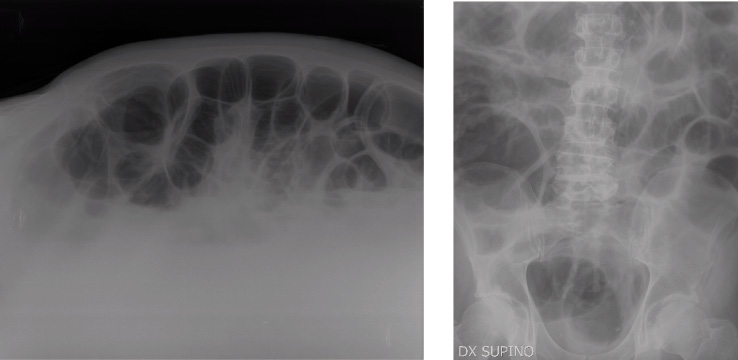

Vengono richiesti, inoltre, Rx torace e Rx diretto dell’addome (Figura 2) che, confrontati con i precedenti, dimostrano un discreto incremento della marcata iperdistensione delle anse tenuali e coliche. Inoltre, l’esame fisico-chimico (presenza di muco e sangue), parassitologico e colturale delle feci per E. coli, Shigella, Salmonella, Clostridium difficile e ricerca di Rotavirus e Adenovirus risultano negativi.

Figura 2. Rx addome eseguito in proiezione frontale in clinostatismo e in proiezione laterolaterale con tubo a bandiera. Si osserva un discreto incremento della marcata iperdistensione delle anse tenuali e coliche. Nel radiogramma eseguito in proiezione laterolaterale con tubo a bandiera si evidenziano alcuni livelli idroaerei. Non falci di aria libera endoperitoneali